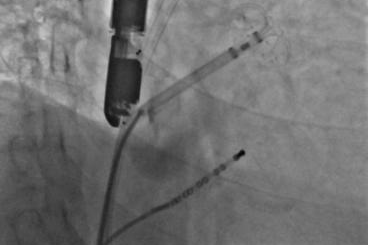

▲半展开固定伞,推送至锚定位锁死血栓

▲释放后,DSA与TEE观察均无残余分流